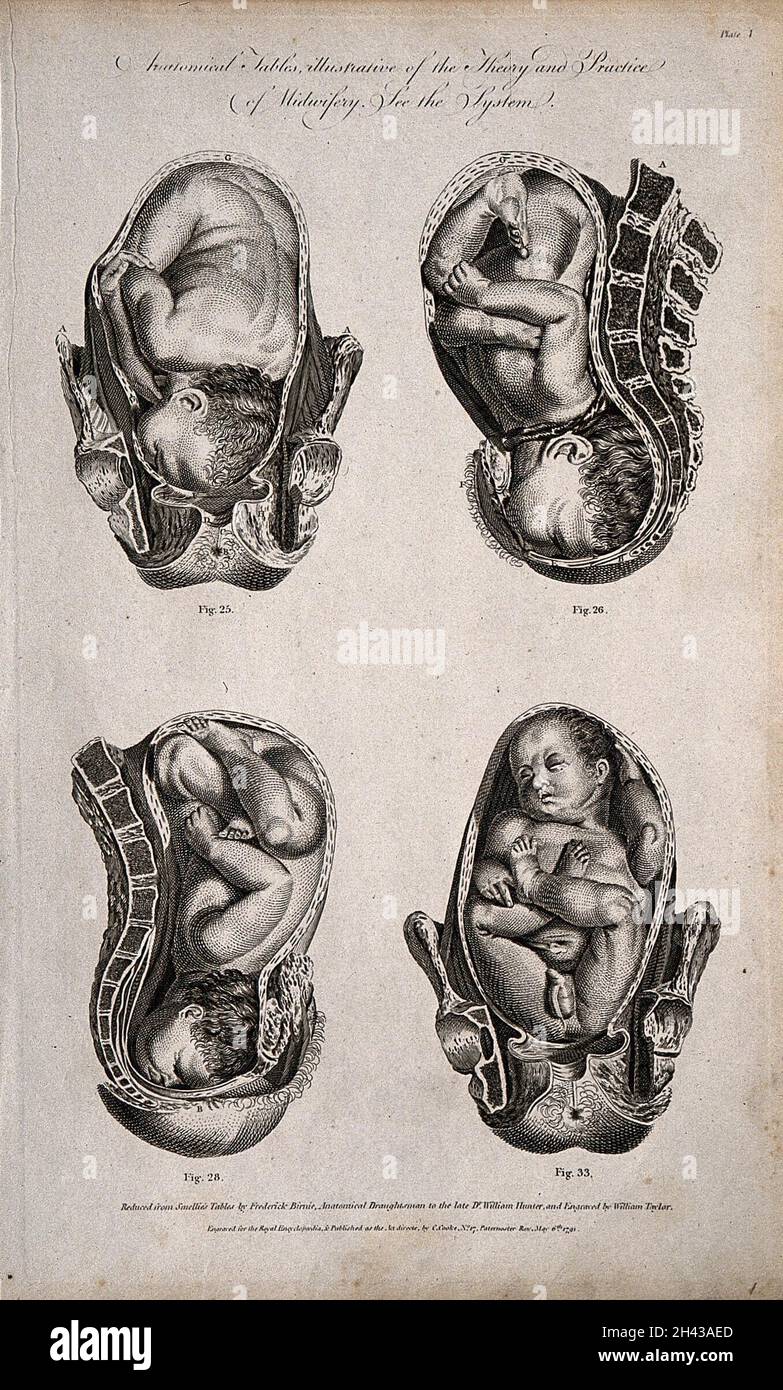

Eight diagrams illustrating babies in the womb in different positions about to enter the world. Etching by Barlow. Stock Photohttps://www.alamy.com/image-license-details/?v=1https://www.alamy.com/eight-diagrams-illustrating-babies-in-the-womb-in-different-positions-about-to-enter-the-world-etching-by-barlow-image449997775.html

Eight diagrams illustrating babies in the womb in different positions about to enter the world. Etching by Barlow. Stock Photohttps://www.alamy.com/image-license-details/?v=1https://www.alamy.com/eight-diagrams-illustrating-babies-in-the-womb-in-different-positions-about-to-enter-the-world-etching-by-barlow-image449997775.htmlRM2H434N3–Eight diagrams illustrating babies in the womb in different positions about to enter the world. Etching by Barlow.